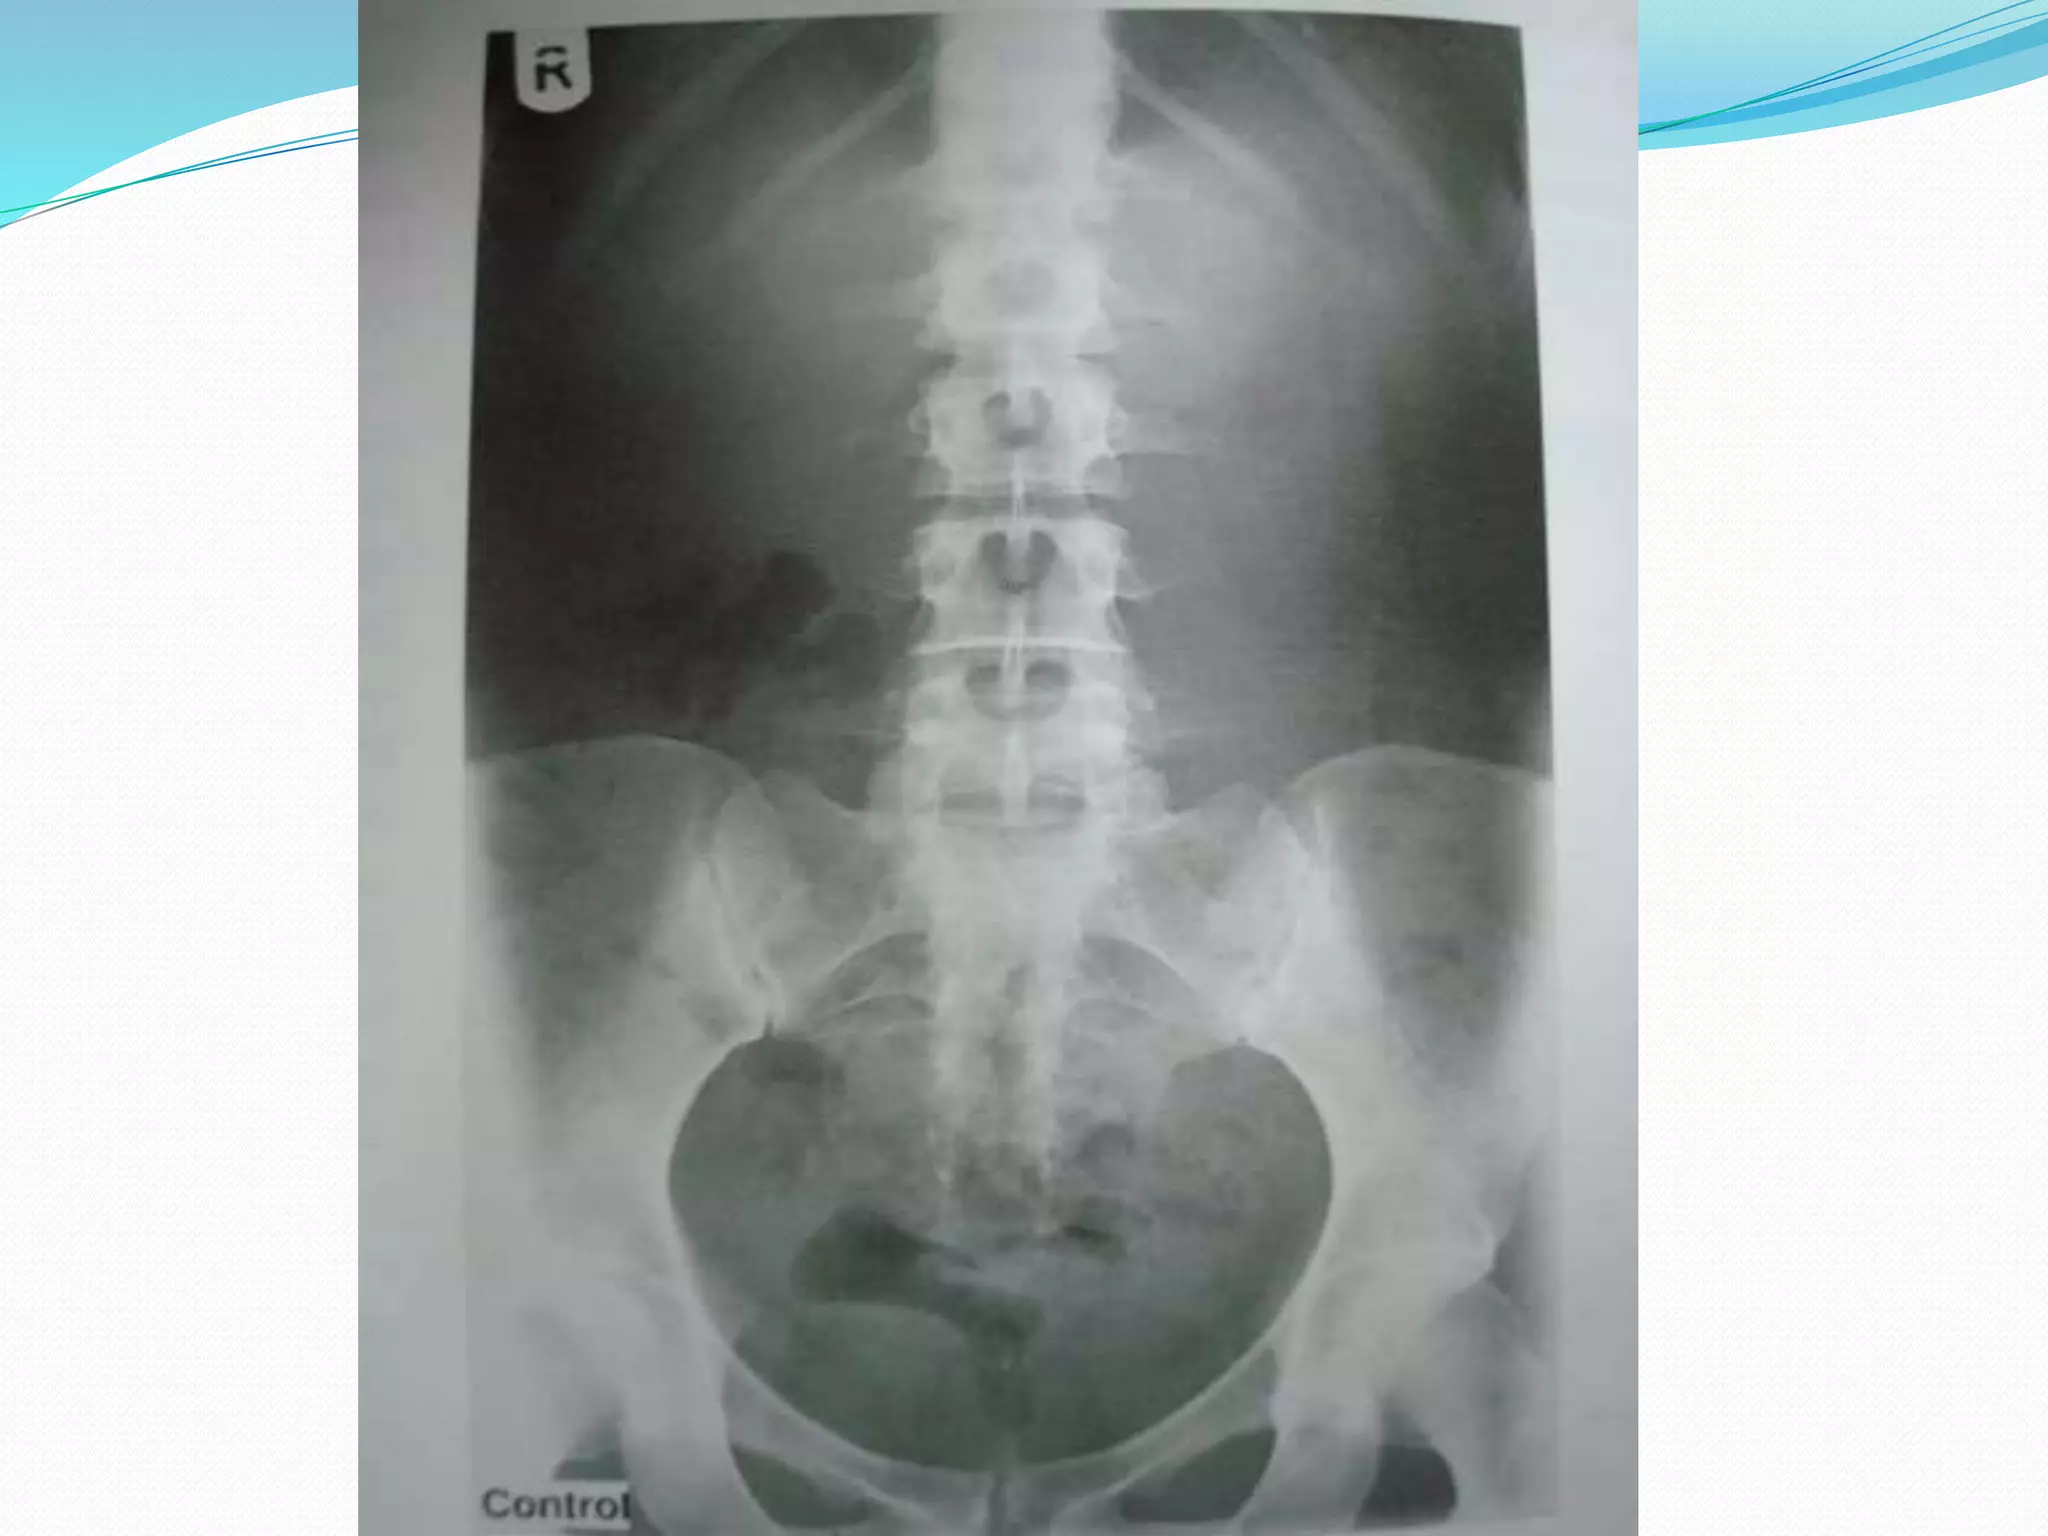

Preliminary/Control film

 Plain film is to demonstrate the urinary tract prior to

administration of contrast medium

 kVp= 70-80 (low kVp), mAs= 60-70

 Centering: the vertical central ray is directed to the

centre of the cassette

 Supine full length AP view of the abdomen in

inspiration.

 Pelvis should be adjusted so that the anterior

superior iliac spines are equidistant from table

top.

 Lower border of cassette is at level of symphysis

pubis.

Why to take preliminary/control film?

 To check exposure factors, centering

 State of bowel preparation

 Obvious pre-existing pathology, particularly urinary

tract calculi/calcification.